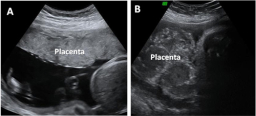

Placenta envejecida y placenta joven

La ecografía 2D nos muestra cómo en una placenta joven, en buen estado, y cómo es una placenta envejecida. En el segundo caso pueden observarse calcificaciones placentarias, lo cual le hace cambiar de textura. Constituye un riesgo para el embarazo al no aportar suficiente oxígeno y...